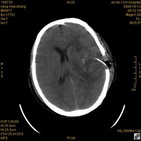

病人杨XX,男,青云街道办事处路踏泉村,住院号51666,CT号:104770。病人因“高血压脑出血”在新泰市人民医院住院治疗5天,治疗效果不佳转入我院,复查CT示左基底节血肿,病人昏迷状态,给予血肿清除术,术后2天复查CT,血肿完全清除,病人恢复好,治疗效果满意。附病人术前术后CT片资料如下。

术后46小时复查CT

术后46小时复查1 术后46小时复查2 术后46小时复查3 术后46小时复查4